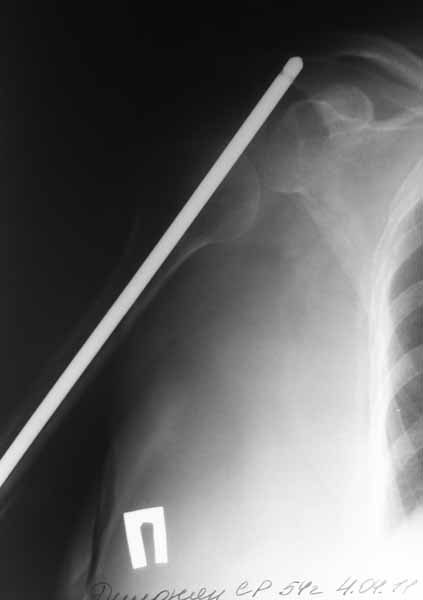

Плечевой сустав на сегодняший день спустя 10 мес. после травмы.

Такое впечатление, что здесь не вывих, но сублюксация головки из-за длительного вынужденного положения, обусловленного особенностью первичного остеосинтеза.

Согласен с Антоном Бехтеревым- здесь скорее всего имеет место выраженная атрофия дельт и как следствие подвывих головки плеча.

Уважаемый коллега на мой взгляд исходя из представленных рентгенограмм и не имея данных клинического осмотра пациентки имеет смысл дифференцировать у пациентки 2 состояния; псевдопаралич (обусловленый массивным поражением ротаторного аппарата выступающим после первичного остеосинтеза фрагментом металлоконструкции) и паралич обусловленный повреждением n axillaris.Возможен также и третий вариант когда имеют место оба повреждения. Уточнив диагноз и нужно будет формировать дальнейшую тактику лечения. С уважением и сожалением Даниленко Олег.

Согласен с коллегой в предположениях, однако склоняюсь к мысли, что имеем дело с нейропатией n. axillaris. Дело в том, что в случае обширного повреждения ВМП нижняя дислокация, как правило, не такая выраженная, т.к. нивелируется за счет тонуса дельтовидной мышцы. Ее вектор тяги направлен в сторону акромиона. Картина очень характерна для паралитической сублюксации. Работает ли дельта? Вы пишете, что пациентка активно зацималась ЛФК. Насколько активно можно заниматься при таком положении штифта? Вероятнее всего он выстоял кпереди от акромиона - это больно, а если под (на снимках не видно)то наличие каких-либо движений вообще сомнительно. Если дельтовидная мышца функционирует, напряжение ее волокон контурируется у худых и ощущается у полных даже при длительном бездействии. Кроме того наличие гипо- или анестезии в дельтовидной области поможет определиться. ЭНМГ прояснит ситуацию.